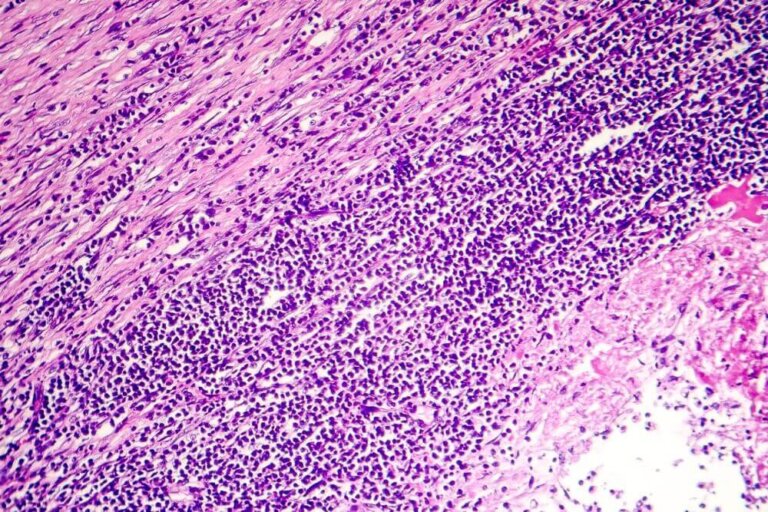

Il pericardio è un sacco fibroelastico a doppio strato che circonda il miocardio, composto da uno strato viscerale che sovrasta l'epicardio e uno strato parietale riccamente innervato, separati da uno spazio che normalmente contiene da 15 a 50 mL di liquido sieroso. Il termine pericardite si riferisce all'infiammazione del sacco pericardico e rappresenta il processo patologico più comune che coinvolge lo stesso. Temporalmente, può essere ulteriormente classificata in pericardite acuta, pericardite incipiente o subacuta, pericardite cronica e pericardite ricorrente. La pericardite può essere associata anche ad altre sindromi pericardiche, come l'effusione pericardica, il tamponamento cardiaco, la pericardite costrittiva e la pericardite effusivo-costrittiva.

Frequentemente, l'infiammazione del pericardio può essere accompagnata da un aumento dell'accumulo di liquido all'interno del sacco pericardico, formando un'effusione pericardica, che può essere sierosa, emorragica o purulenta a seconda dell'eziologia. Questo accumulo di liquido può diventare emodinamicamente significativo, soprattutto quando l'effusione pericardica è ampia o il tasso di accumulo è troppo rapido, poiché il liquido può comprimere esternamente le camere cardiache limitando il riempimento diastolico e causando la sindrome del tamponamento cardiaco. Questo può manifestarsi con shock ostruttivo ed è considerato un'emergenza medica che richiede un intervento immediato. Inoltre, la pericardite può essere seguita da ispessimento del pericardio, che può presentarsi raramente come pericardite costrittiva in mesi o addirittura anni dopo che l'insulto iniziale è passato. Un'entità descritta più di recente chiamata pericardite effusivo-costrittiva, si verifica quando c'è accumulo di liquido intorno al miocardio, ma si manifesta una fisiologia costrittiva anche dopo che è stata eseguita una pericardiocentesi, segnalando una patologia costrittiva indipendente dalla presenza di una effusione pericardica.